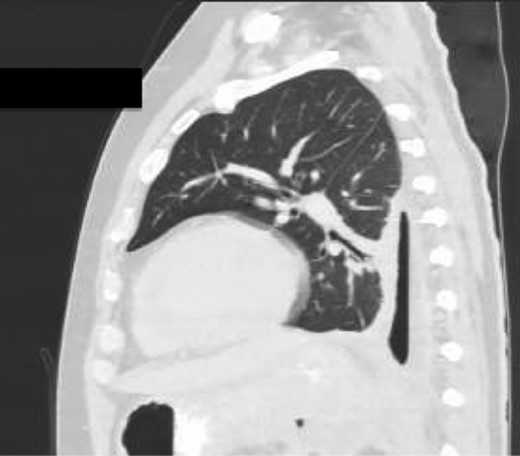

Chest X-ray in ICU following drainage showed what was thought to be Pneumomediastinum (Figs 1 and 2), and given this concern he was referred to the Cardiothoracic service. Subsequent CT suggested a large loculated hydro-pneumothorax, which in retrospect represented the drained Pseudocyst communicating through the diaphragm (Figs 3 and 4).

Sagittal view CT Chest revealing large residual space with loss of left lung volume due to the pseudocyst. Image post-transgastric drainage.